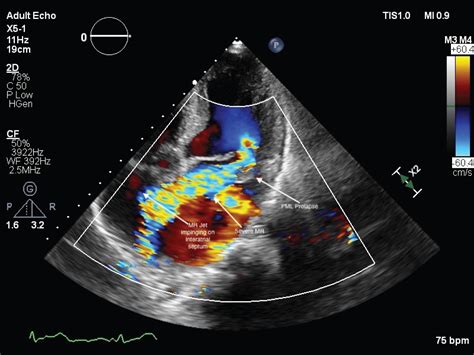

• Echocardiogram: This ultrasound test provides detailed images of the heart's structure and function, allowing doctors to visualize the aneurysm.

• Transesophageal Echocardiogram (TEE): This more invasive procedure involves inserting a probe down the throat to get a clearer view of the heart's structures.